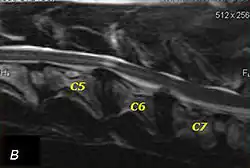

The disease tends to be gradually progressive. Symptoms such as weakness, ataxia, and dragging of the toes start in the rear legs. Dogs often have a crouching stance with a downward flexed neck. The disease progresses to the front legs, but the symptoms are less severe. Neck pain is sometimes seen. Symptoms are usually gradual in onset, but may progress rapidly following trauma.[6] X-rays may show misaligned vertebrae and narrow disk spaces, but it is not as effective as a myelogram, which reveals stenosis of the vertebral canal. Magnetic resonance imaging has been shown to be more effective at showing the location, nature, and severity of spinal cord compression than a myelogram.[7] Treatment is either medical to control the symptoms, usually with corticosteroids and cage rest, or surgical to correct the spinal cord compression. The prognosis is guarded in either case. Surgery may fully correct the problem, but it is technically difficult and relapses may occur. Types of surgery include ventral decompression of the spinal cord (ventral slot technique), dorsal decompression, and vertebral stabilization.[8] One study showed no significant advantage to any of the common spinal cord decompression procedures.[9] Another study showed that electroacupuncture may be a successful treatment for Wobbler disease.[10] A new surgical treatment using a proprietary medical device has been developed for dogs with disc-associated wobbler disease. It implants an artificial disc (cervical arthroplasty) in place of the affected disc space.[11]